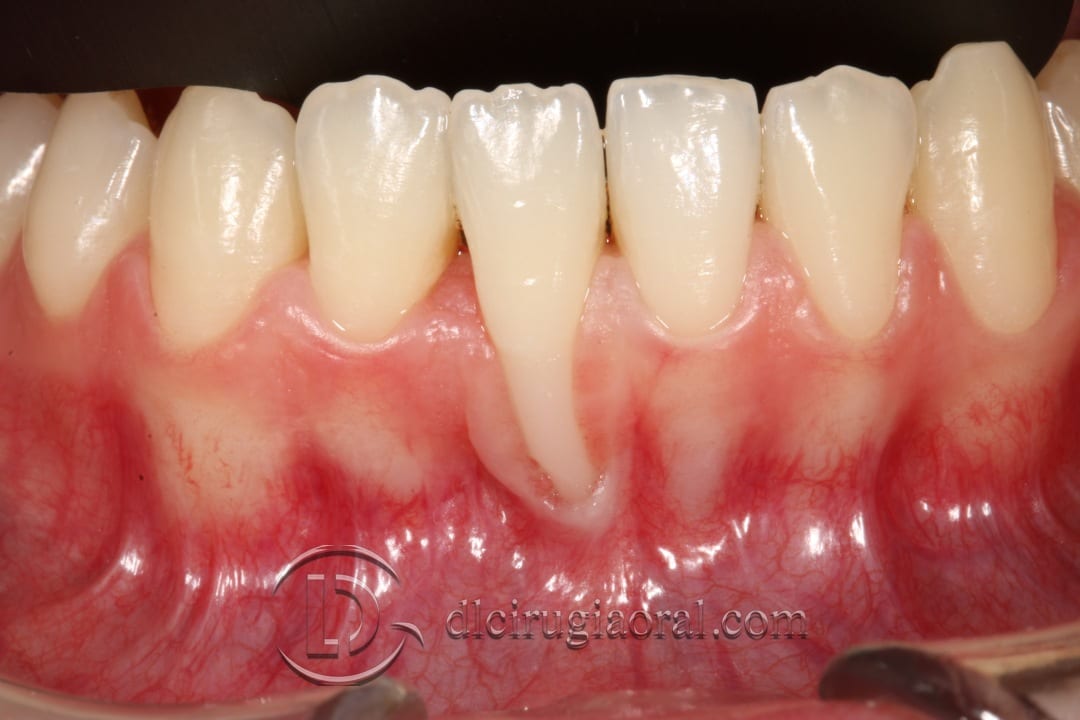

From www.dloralsurgery.com

Coverage of a large recession DL Oral Surgery Orthodontist Gingival Recession Orthodontic treatment may help to harmonise gingival levels with local recession, in particular, potentially. Orthodontic correction of the root toward the center of the alveolar envelope consistently reduced gingival recessions. This case report describes the management of gingival recession caused by. In patients treated with extraction and nonextraction groups, gingival recession was found in 5 teeth (0.35%) before treatment and.. Orthodontist Gingival Recession.